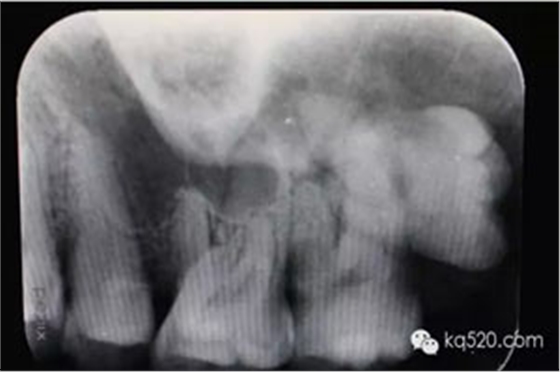

圖2.根尖片檢查:28遠(yuǎn)中水平阻生,看不清28牙根與上頜竇的關(guān)系,建議拍全景片。